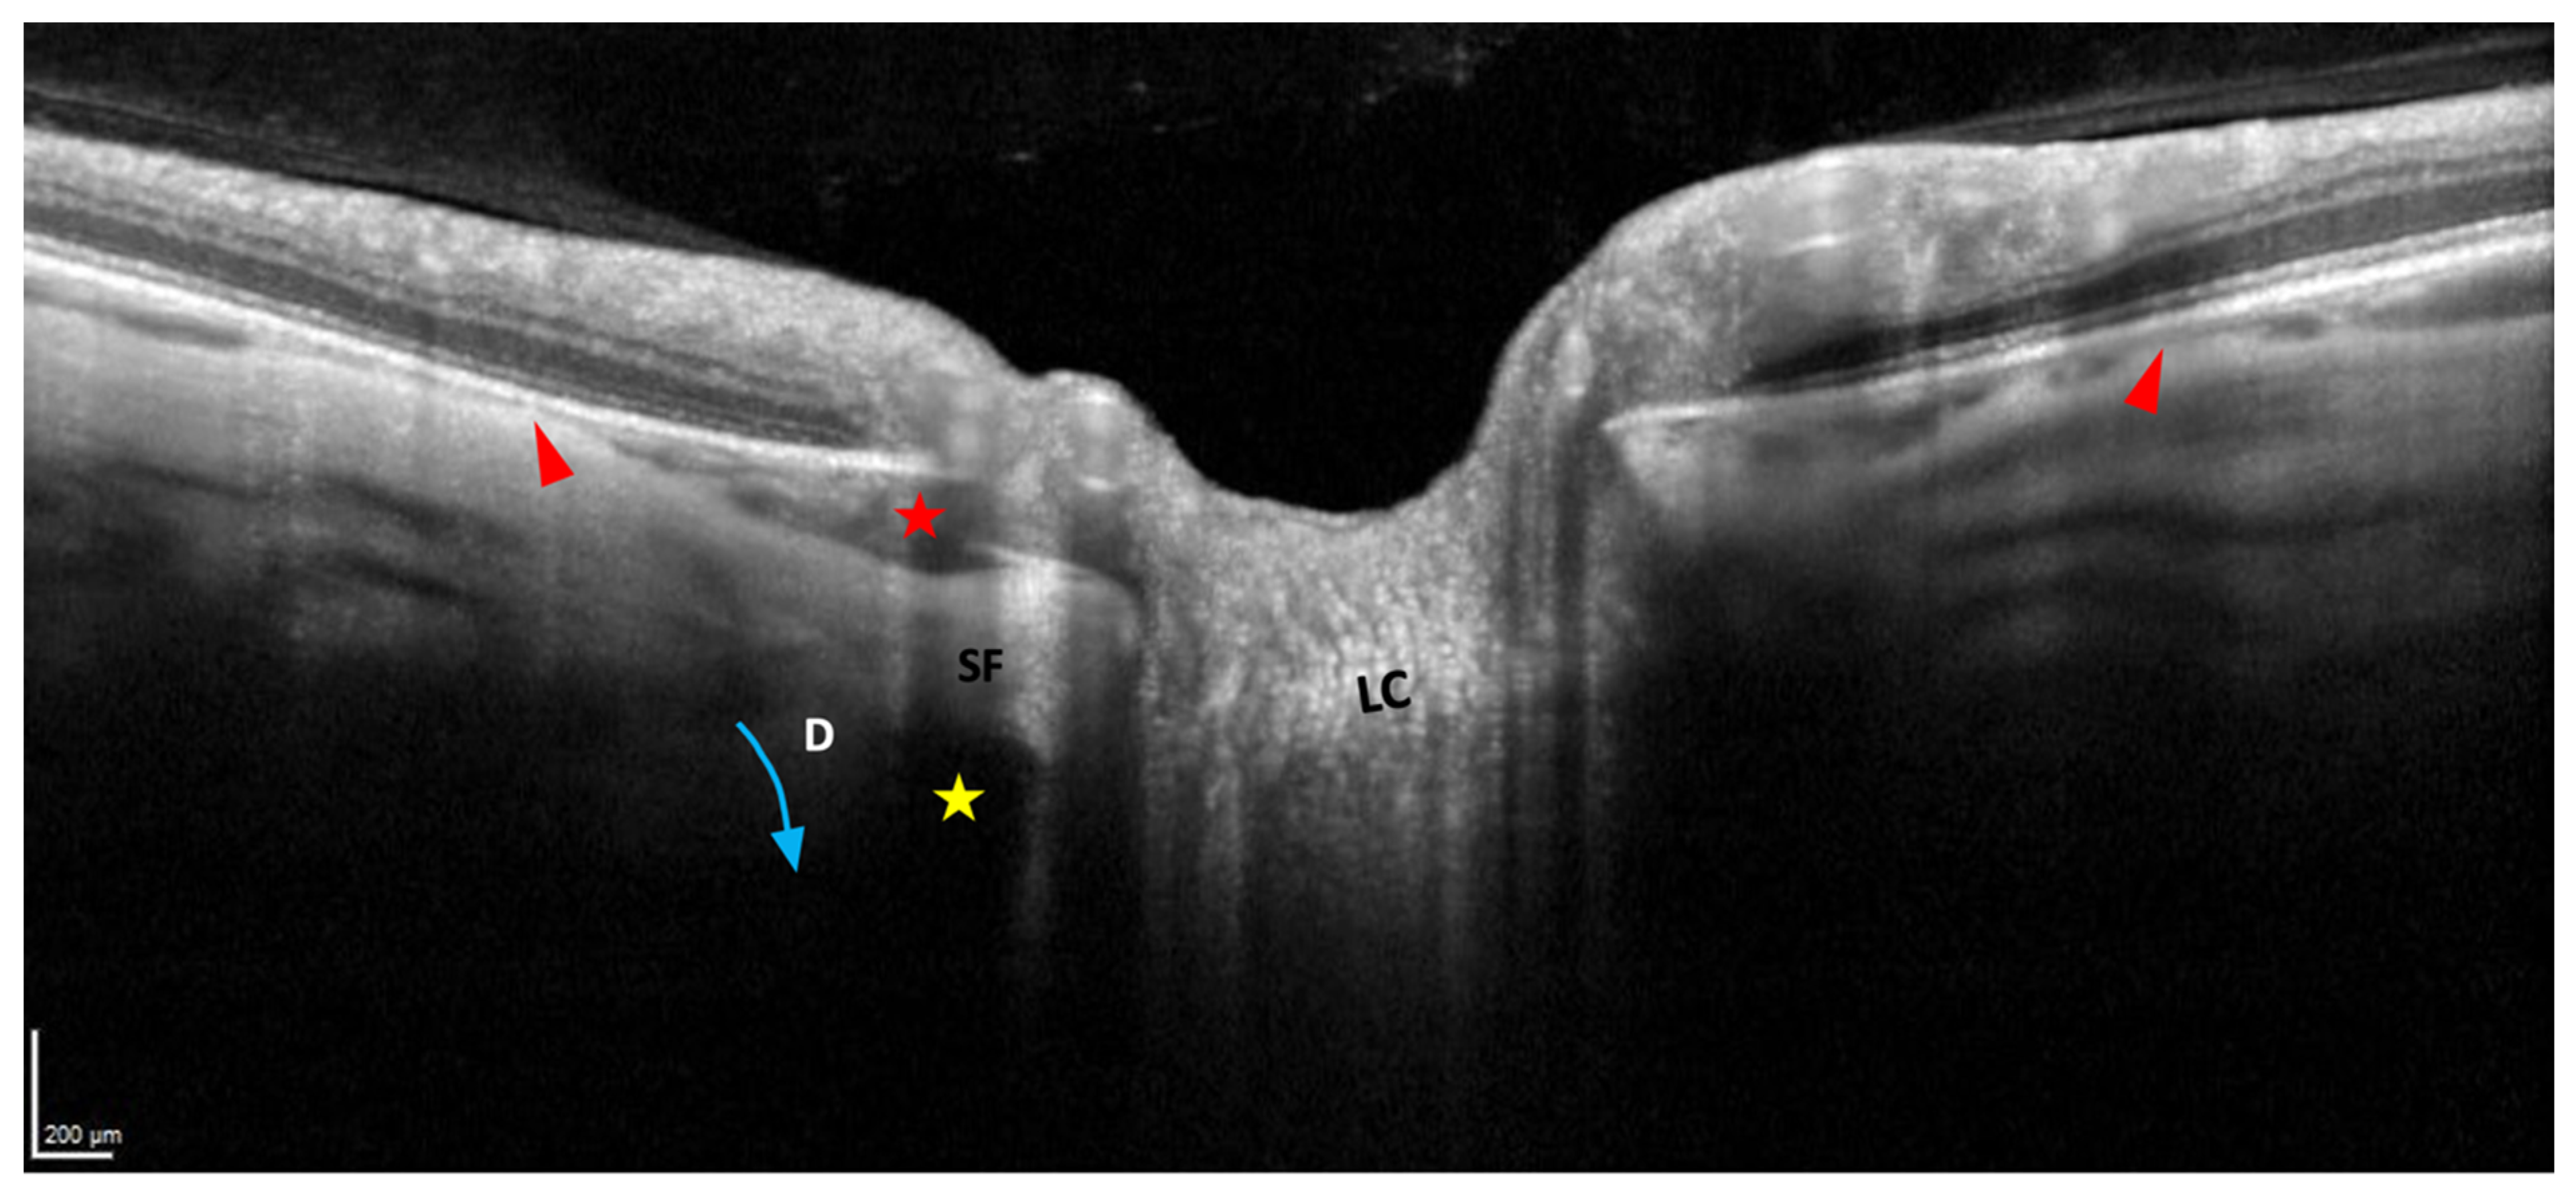

5.4. Border Tissue of the Choroid

7.2. PICC and Glaucoma

8. Pathogenetic Hypotheses of PICC

8.3. Mechanical Considerations

8.3.1. PICC as a Complication of Peripapillary Staphyloma

8.3.2. PICC as a Complication of Myopic Tilted Disc and Myopic Conus

8.3.3. PICC as a Complication of the Optic Nerve Sheaths Traction